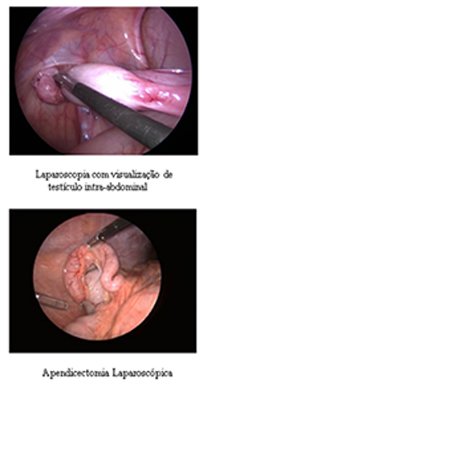

Para se tornar um Cirurgião Pediátrico, o médico precisa fazer dois anos de residência em Cirurgia Geral e mais três anos de residência em Cirurgia Pediátrica, onde verá as diferenças existentes no tratamento dispendidos a um adulto e a uma criança, ganhando habilidade no manuseio desses pacientes tão especiais. Normalmente as cirurgias são mais delicadas, realizadas sob anestesia geral e não necessitam de dormir no hospital (porém muitas delas podem ser realizadas em regime de Hospital Dia com internação que varia de 6 a 12 h). Casos cirúrgicos comuns em crianças são as hérnias inguinal e umbilical, cistos da região do pescoço como os branquiais e o tireoglosso, testículos que não estão situados na bolsa testicular, hipospádia e outras malformações do aparelho urinário, fimose, anquiloglossia (“língua presa”), tumores e doenças gastrointestinais.